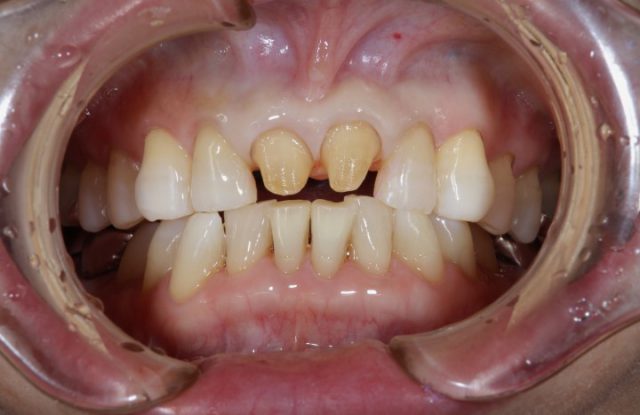

施術後

術後の画像を見ていただいても分かりますようにまわりの歯と比べてもとても自然に仕上がります。おそらく近くでじっと見られても被せものであるとは分からないほど自然です。患者さまご本人も被せ物の仕上がりにとても喜んでおられました。